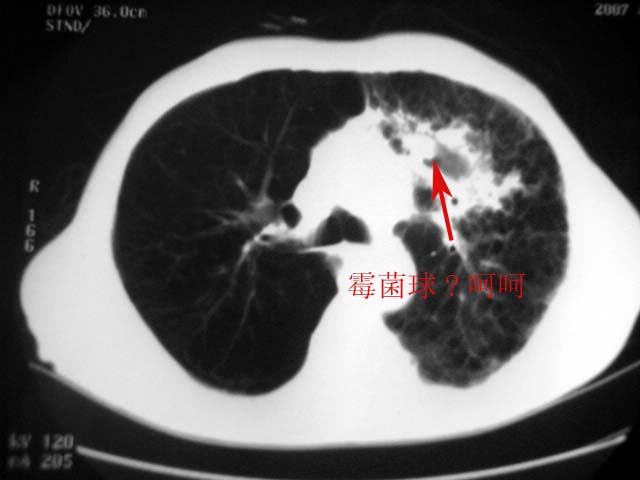

以下是引用zjzjr在2007-9-4 17:00:00的发言:[br]双上肺继发型结核伴左上肺空洞形成.慢性支气管炎伴肺气肿.